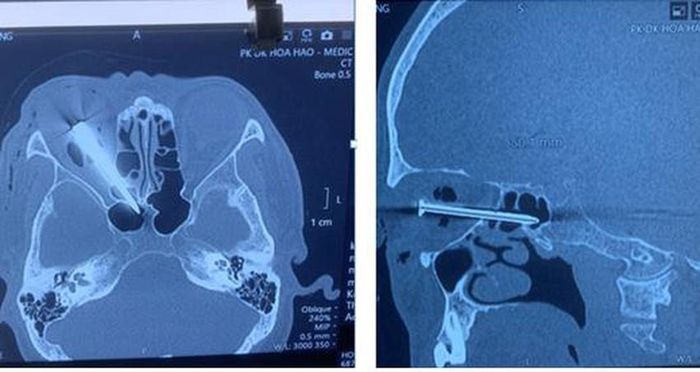

Ông NVH bị cây đinh dài 5 cm đâm xuyên mắt phải trong lúc giăng dây để đóng cốt pha đổ bê tông.

Sáng 24-6, BS Trần Văn Sóng, Phó Giám đốc Bệnh viện (BV) Nhân dân 115 TP.HCM, cho biết nơi đây vừa điều trị trường hợp hy hữu: Cây đinh dài 5 cm xuyên qua mắt phải.

Cây đinh dài 5 cm đâm xuyên mắt phải ông H. Ảnh: BVCC

Tại đây, các BS nhận định dị vật là cây đinh dài 5 cm xuyên ổ mắt phải qua xoang sàng, xoang bướm. Chưa hết, đầu nhọn cây đinh đâm cạnh trái khe thần kinh thị mắt phải và nằm gần thành trái xoang bướm phải.